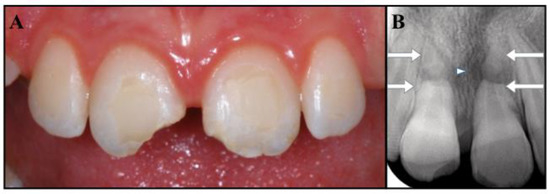

The follow-up was carried out according to schedule. At 30 months, the patient was free of symptoms, and the periapical radiographs showed healthy periodontal tissues around both the fractured roots and the apical fragments, while the fractured areas seemed to have healed, with hard tissue deposition (Figure 4C,D). The tooth eruption was assessed to be normal with the continued development of the alveolar ridge. Undesirably, tooth # 2.1 showed mild signs of discoloration. The patient was informed that the clinical and radiographic follow-up would continue once a year for at least another three years, and ideally for as long as possible. She was also made aware that further considerations will be necessary upon completion of the permanent dentition.

Figure 4.

(A,B) Clinical photograph and intraoral radiographs of teeth #1.1 and #2.1 at the initial stage of treatment (replantation) and at the 30-month follow-up. (C,D) The images show good coronal restorations, mild signs of discoloration in the cervical portion of tooth #2.1, healing in the fracture lines, a healthy periapex.

The complexity of this case derives from the combination of root fractures with the avulsion of the coronal fragments, which places the traumatic injury into two different categories (Figure 1B). Fortunately, it was possible to merge the recommendations [1,2,13] and provide a reasonable treatment plan. At 30 months, the patient was asymptomatic, the replanted fragments did not exhibit mobility or a metallic percussion sound, and radiographs showed no evidence of infection-related or ankylosis-related resorption. The application of an apexification treatment to the coronal segments has enabled the healing of apical periodontitis and the repair of the fractured ends of the roots, while the apexes seem to have maintained their vitality, as shown by the lack of symptoms and clinical and radiographic signs (Figure 4C,D). The only unfavorable outcome was represented by a mild discoloration detected in the cervical area of tooth # 2.1.